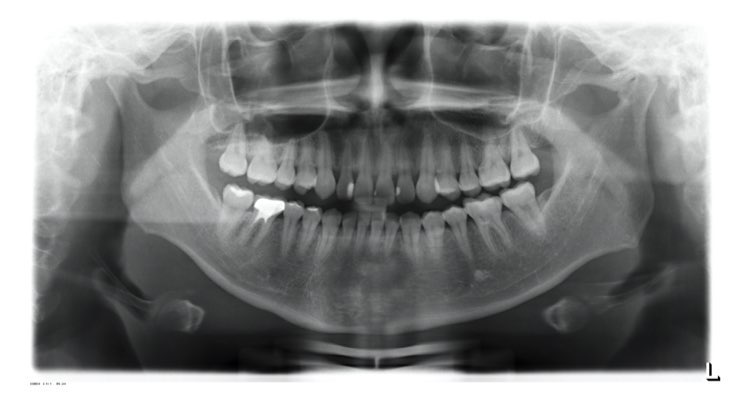

全景X光片诊断

牙齿综合检查报告